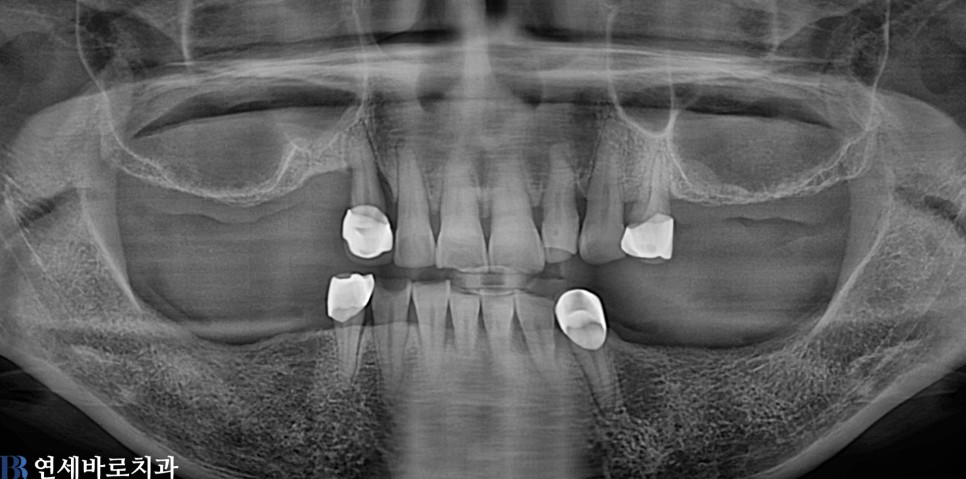

임플란트

양쪽 어금니 임플란트 치료 #2